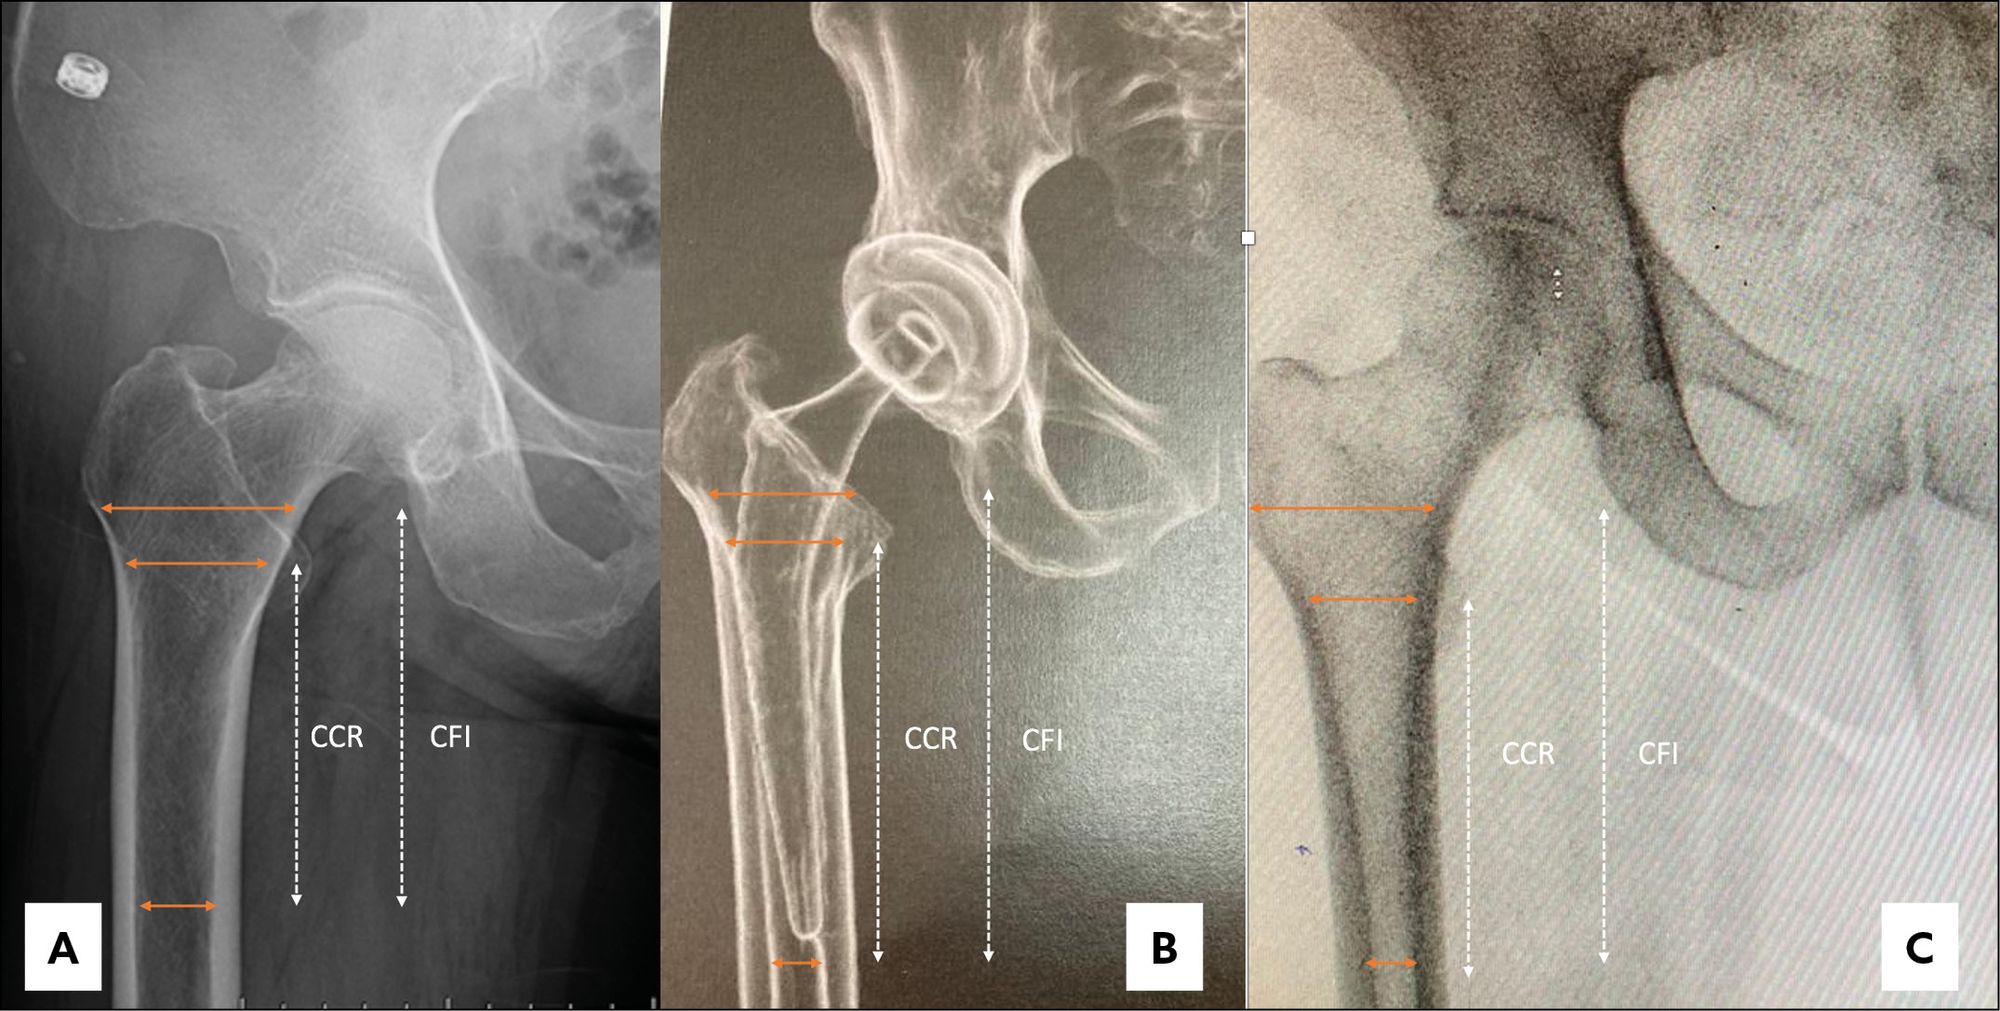

Femur shape was determined using the canal flare index (CFI) as measured on the preoperative x-rays.[15] Noble PC, Alexander JW, Lindahl LJ, Yew DT, Granberry WM, Tullos HS. The Anatomic Basis of Femoral Component Design. Clin Orthop Relat Res. 1988 CFI was defined as the width of the medullary canal 2cm above the lesser trochanter, divided by the width of the canal 10cm below the lesser trochanter. Using the criteria established by Noble et al., [15] Noble PC, Alexander JW, Lindahl LJ, Yew DT, Granberry WM, Tullos HS. The Anatomic Basis of Femoral Component Design. Clin Orthop Relat Res. 1988 a CFI < 3.0 was classed as a stovepipe canal shape, a CFI between 3.0 and 4.7 was classed as normal canal shape, and a CFI > 4.7 was classed as a champagne-fluted canal shape (Fig. 3). The canal calcar ratio (CCR) [16] Dorr LD. Total hip replacement using APR system. Tech Orthop. 1986 was also measured to establish femoral shape according the Dorr classification. [17] Issa K, Stroh AD, Mont MA, Bonutti PM. Effect of bone type on clinical and radiographic outcomes of a proximally-coated cementless stem in primary total hip arthroplasties. J Orthop Res Off Publ Orthop Res Soc. 2014 CCR was defined as the width of the medullary canal 10cm below the lesser trochanter, divided by the width of the canal at the lesser trochanter. A CCR < 50% was classified as Dorr type A, a CCR between 50 and 75% was classified as Dorr type B, and a CCR > 75% was classified as Dorr type C. Radiographic analysis was performed independently by two senior surgeons who knew neither the patient identity nor the surgical approach used.